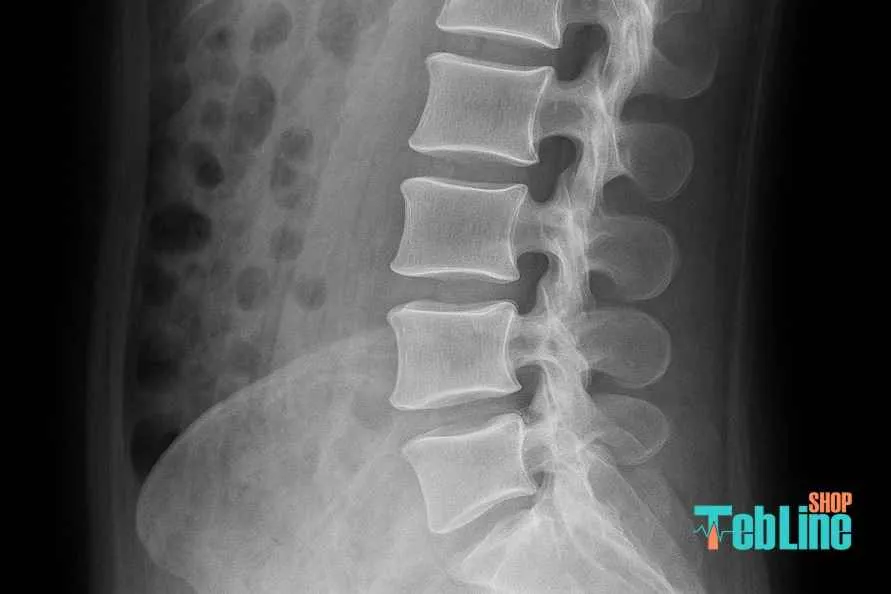

ستون فقرات انسان از مهرههایی تشکیل شده که بین آنها بالشتکهای انعطافپذیری به نام دیسک بینمهرهای قرار دارند.

این دیسکها مانند کمکفنر عمل میکنند؛ یعنی هنگام خم شدن، نشستن یا بلند کردن اجسام، فشار وارده را جذب و پخش میکنند تا به مهرهها آسیبی نرسد.

سطح درگیری دیسک تعیینکننده مسیر درد است

در ستون فقرات کمری معمولاً دو نقطه بیش از بقیه درگیر میشوند:

L4–L5

L5–S1

این دو سطح دقیقاً همان جاهایی هستند که اعصاب به پاها میروند،

و به همین دلیل بیشتر بیماران در این نواحی درد منتشره دارند.

دیسکهای ناحیه کمری از بالا به پایین نامگذاری میشوند (L1 تا S1).

اما شایعترین محل آسیب، دو ناحیهی L4–L5 و L5–S1 است.

روشهای تصویربرداری برای تشخیص دقیق

اگر درد بیشتر از دو هفته طول بکشه یا علائم عصبی وجود داشته باشه، پزشک معمولاً درخواست MRI میده.

MRI بهترین روش برای دیدن وضعیت واقعی دیسک و میزان فشردگی عصبهاست.

در موارد سادهتر یا برای غربالگری، ممکنه از X-ray یا CT Scan استفاده بشه، ولی اینها فقط شکل کلی استخوانها رو نشون میدن، نه خود دیسک.